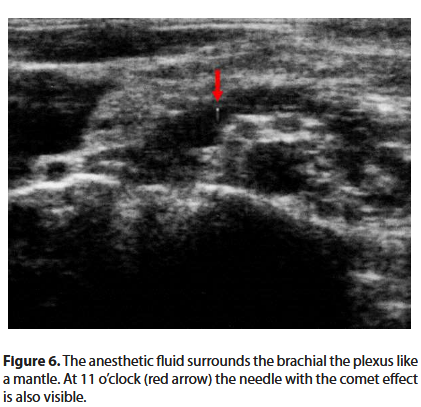

The electrostimulator is set with a current of 0.4 mA. The needle is slowly advanced. When the desired twitch (deltoid, biceps or triceps muscle) appears, the intensity of the current is reduced to below 0.2 mA, until the twitch disappears. In this way we are sure that the tip of the needle is not intraneural. Once the previous stimulation values are restored, 1 ml of anesthetic solution is injected followed by a paraesthesia and the disappearance of the twitch (Raj test) [6]. Only now can we inject the anesthetic solution, witnessing on the screen the expansion of the liquid in the neurovascular bundle (Figures 6 and 7).